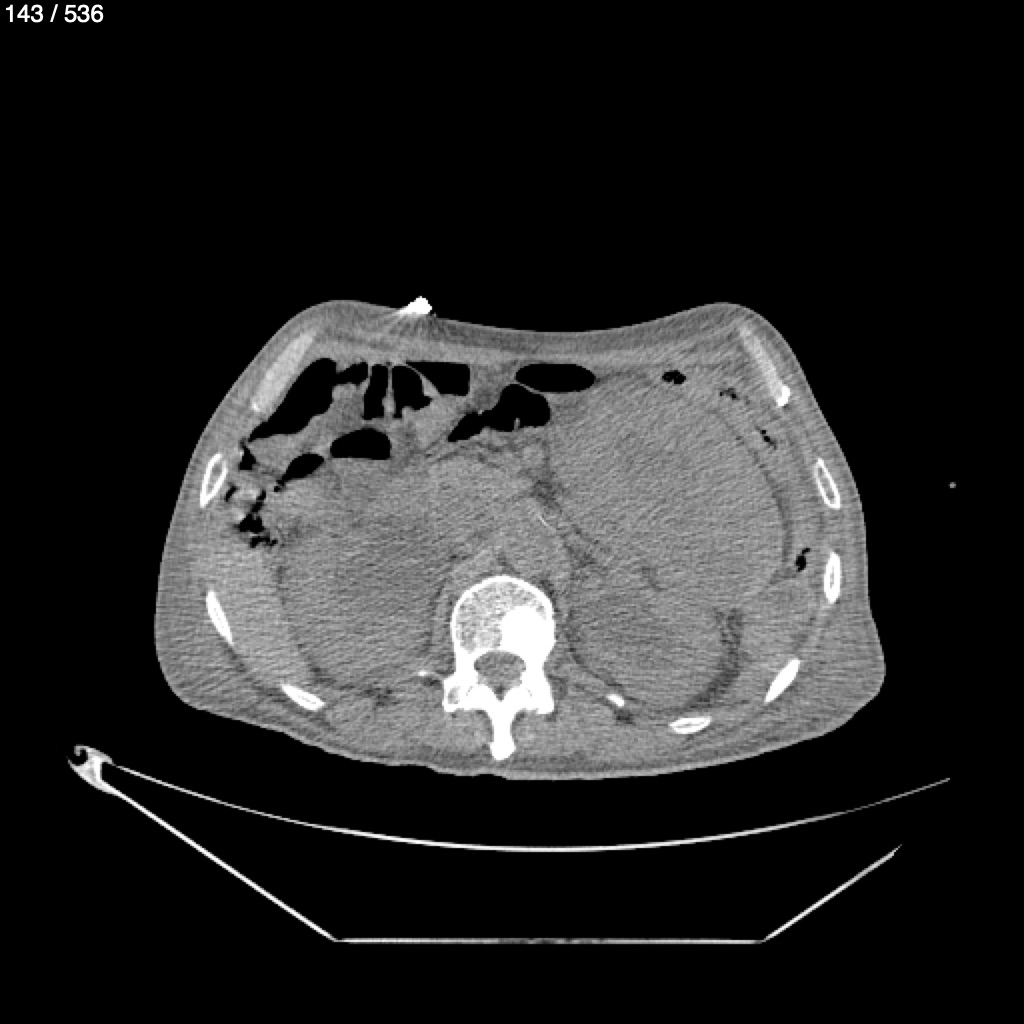

Angel Villalobos Palomeque 73 A - T.C Abdomen Simple